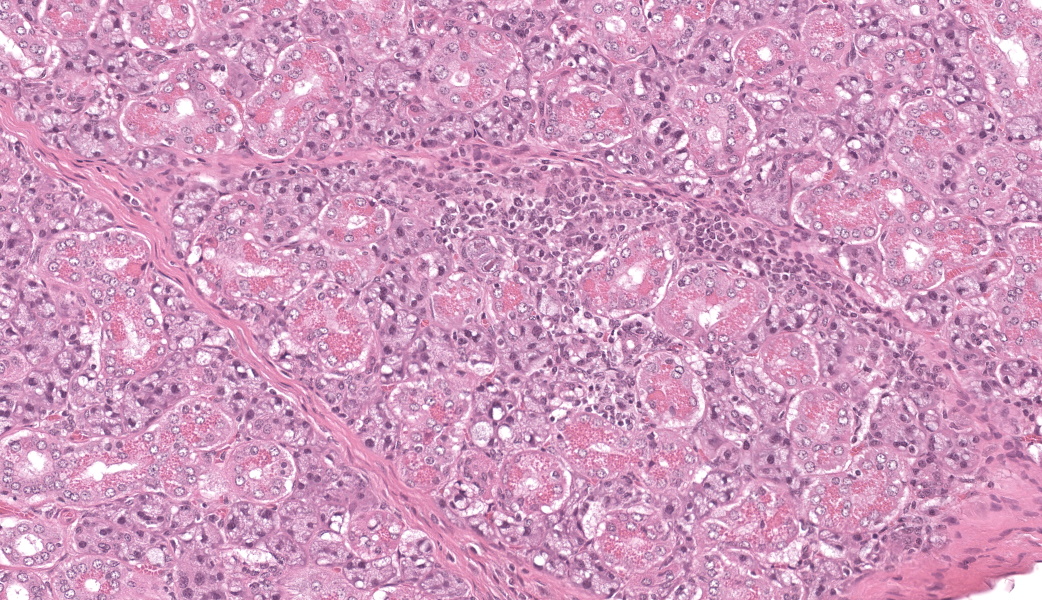

Microscopic Description:

Few acinar and stromal cells with markedly enlarged nuclei and abundant cytoplasm (cytomegaly) with 8-12 µm eosinophilic intranuclear inclusions were scattered throughout the submandibular salivary gland with accompanying lymphoplasmacytic infiltration in several regions.p

Sialoadenitis, multifocal, subacute to chronic, mild with epithelial and stromal cytomegaly and intranuclear inclusions (cytomegalovirus)p

The most frequently encountered lesions occur in the submandibular salivary glands and rarely in the parotid glands, with excretion in saliva serving as the primary means of transmission through grooming and biting activities. Typical histological findings include eosinophilic intranuclear and intracytoplasmic inclusions in acinar epithelial cells with cytomegaly and interstitial lymphoplasmacytic inflammation.6 Intranuclear inclusions result from viral DNA replication within the nuclei of infected cells, while intracytoplasmic inclusions represent replication processes that occur in the cytoplasm, including production of the capsid protein.8

Salivary gland: Sialoadenitis, lymphoplasmacytic, chronic, multifocal, mild, with epithelial karyomegaly and intranuclear viral inclusions.